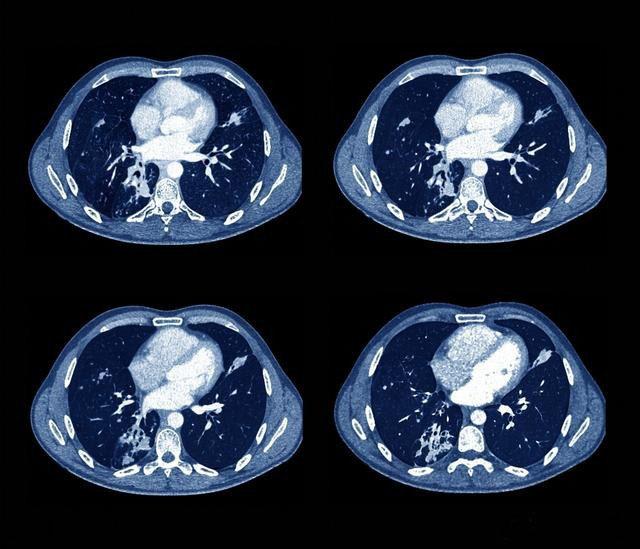

结核菌对人体具有巨大的破坏作用,特别是肺组织,可引起支气管狭窄,造成肺不张,是一部分非失去作用,严重影响肺功能,同时,肺组织别破坏排出体外后可在肺部留下空洞,有些肺部空洞不能自行闭合,会长时间的存在,洞壁上生长着很多结核菌,这种形态的病灶也是传染源之一。

结核还会留下诸多后遗症,比如支气管扩张,一旦形成,就难以根治,支气管扩张不但会造成病人长期咳嗽咳大量痰液,还会引起肺部感染,导致患者发热,严重时,支气管扩张还会导致咯血,支气管扩张和肺结核是咯血的两个最常见原因。